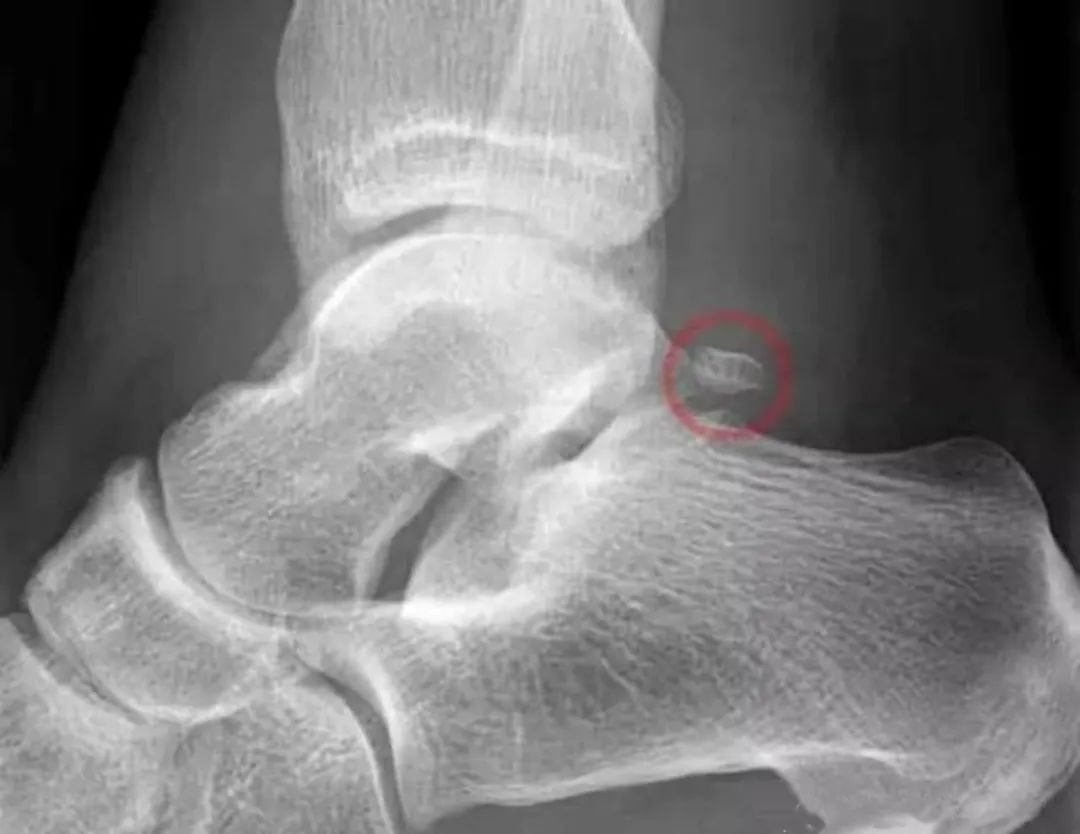

X线片检查:主要判断关节位置以及有无明显骨赘增生。

X线片检查可见后踝部位出现骨赘增生,在踝关节跖屈位会出现后踝的撞击